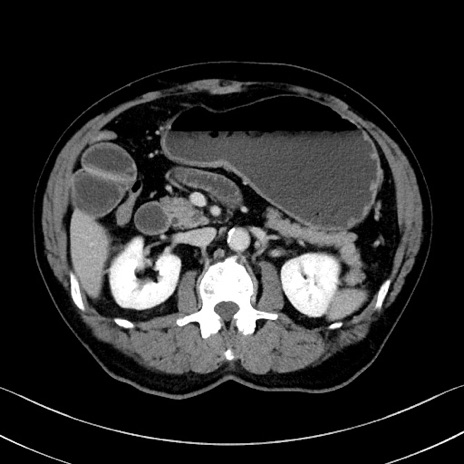

症例35(横断像)

【症例】70歳代 男性

【主訴】腹部膨満、嘔吐

【現病歴】昨日より腹部膨満感出現。本日増悪し、仙痛出現。嘔吐あり、受診。

【既往歴】糖尿病、胆摘後

【身体所見】BP 149/80mmHg、HR 74/min、BT 35.9℃、腹部:膨満、軟、圧痛なし。腸雑音減弱あり。上腹部正中切開瘢痕あり。

【データ】WBC 13500、CRP 1.72